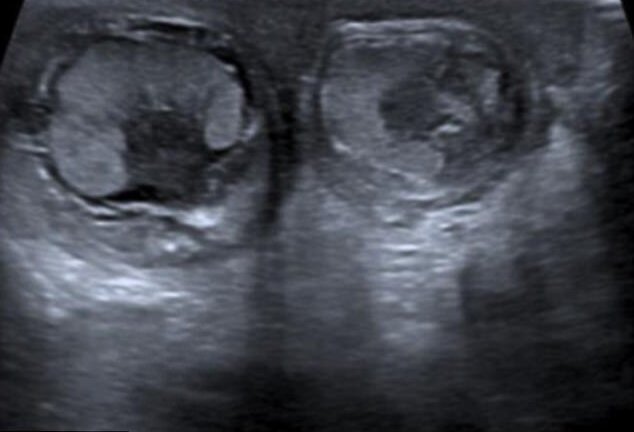

Cậu bé bị xoắn cả hai tinh hoàn trong bụng mẹ

Một em bé ở Anh sinh ra với tinh hoàn "to và lớn" bị xoắn cả hai bên trong tử cung của người mẹ.